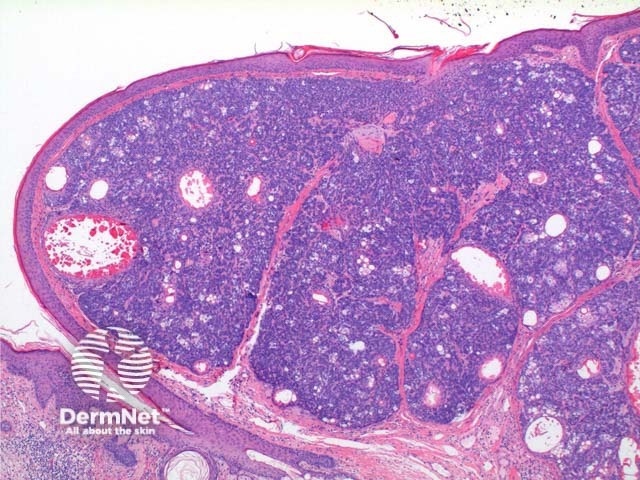

Scanning power of the histology of sebaceoma demonstrates a relatively well-circumscribed tumour nodule typically within the deep dermis frequently with attachment to the epidermis. Low power identifies a lobulated tumour, which may demonstrate areas of cyst formation (Figure 1). The tumour is comprised of basaloid cells and a minority of sebaceous cells in addition to small ducts with the crenelated eosinophilic lining seen in sebaceous ducts (Figures 2, 3 and 4). A variable number and distribution of sebocytes is seen, but should remain the minor proportion compared to the basaloid component. Frequent mitoses can be seen in this tumour, though cytological atypia is lacking (Figure 5).

Figure 1